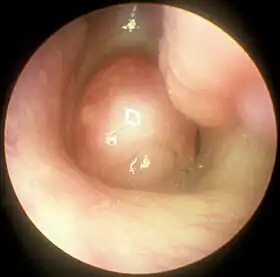

Nasal polyp

| A nasal polyp | |

Nasal polyps (NP) are noncancerous growths within the nose or sinuses.[1] Symptoms include trouble breathing through the nose, loss of smell, decreased taste, post nasal drip, and a runny nose.[1] The growths are sac-like, movable, and nontender, though face pain may occasionally occur.[1] They tend to be smooth, rounded, soft, pale or yellowish, and they appear shiny and attached to the inside of the nose by a small stalk or pedicle.[4] They typically occur in both nostrils in those who are affected.[1] Complications may include sinusitis and broadening of the nose.[2]

Nasal polyps can be seen on physical examination inside of the nose and are often detected during the evaluation of symptoms. On examination, a polyp will appear as a visible mass in the nostril.[6] Some polyps may be seen with anterior rhinoscopy (looking in the nose with a nasal speculum and a light), but frequently, they are farther back in the nose and must be seen by nasal endoscopy.[13] Nasal endoscopy involves passing a small, rigid camera with a light source into the nose. An image is projected onto a screen in the office so the doctor can examine the nasal passages and sinuses in greater detail. The procedure is not generally painful, but the person can be given a spray decongestant and local anesthetic to minimize discomfort.[14]